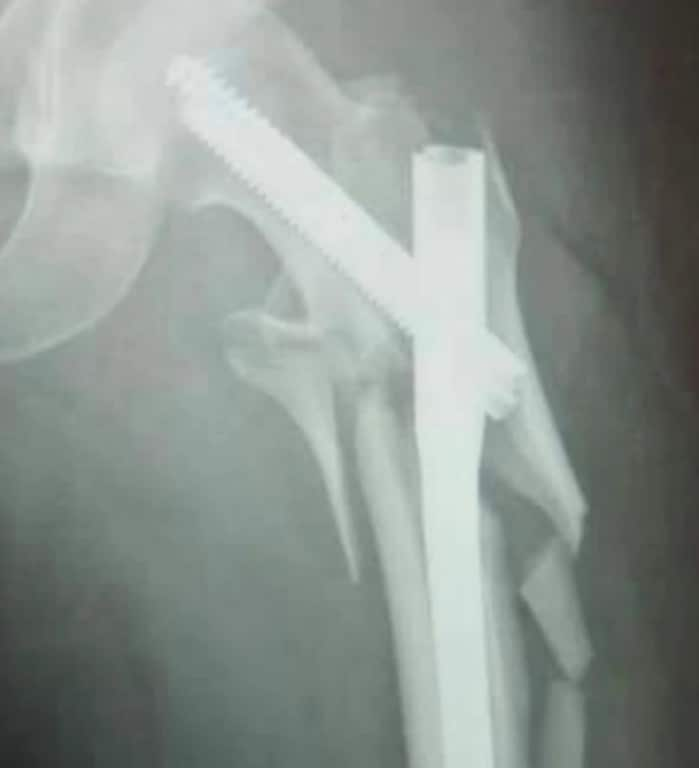

納沙腿部骨折。 Source: Supplied

納沙在庭外表示,他因受傷要接受多次手術,目前仍嚴重影響其腿部活動。他因此失去工作,希望賠償能幫補他康復,並重返職場。「我只能改變我能控制的事。」